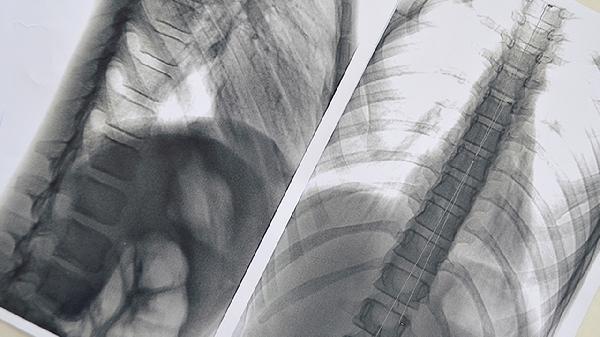

1、CT检查

胸部高分辨率CT是评估肺结节良恶性的首选方法。恶性结节常表现为边缘毛刺、分叶状、胸膜凹陷等特征,良性结节多呈圆形光滑、钙化均匀。薄层CT可清晰显示结节内部结构,增强CT有助于观察血流特征。磨玻璃样结节需特别关注持续存在的非钙化病灶。